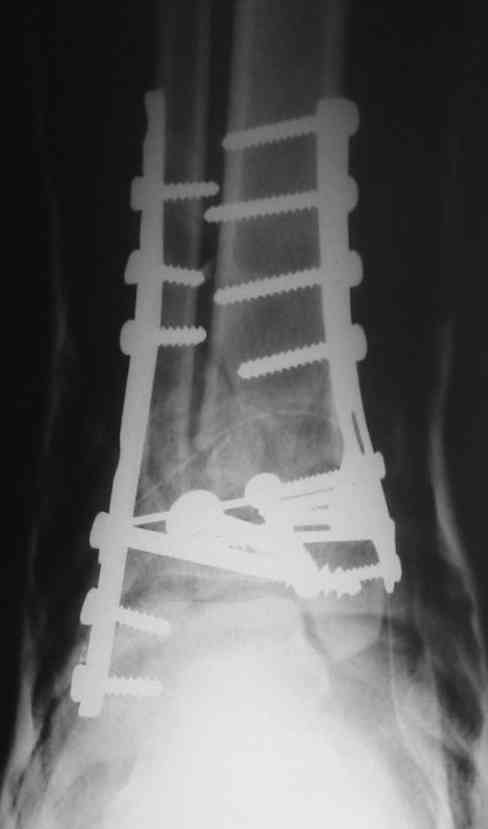

Ja operiroval bolnogo po Vashemu, hotia sam ni ochen' ubezden' v itom, t.k. bolnoi otkazalsa na proch' ot ex.fix, ja emu sdelal ORIF + Kostnia plastika, snimky prelogiottsa,